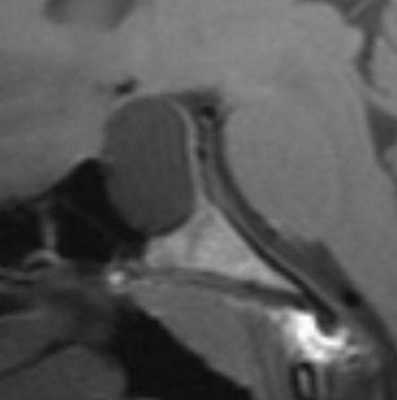

На изображениях ниже можно посмотреть, как киста Ратке выглядит на снимке .

МРТ: киста кармана Ратке. На Т1-взвешенном сагиттальном изображении, полученном до введения контраста, заметно четко очерченное образование в области турецкого седла - с распространением в супраселлярную цистерну. Отмечается гомогенно высокая интенсивность сигнала в образовании по сравнению с паренхимой головного мозга.

![f2]()

Т2-взвешенное аксиальное изображение (тот же пациент, что и на предыдущем изображении).

![f3]()

Т2-взвешенное аксиальное изображение: изоинтенсивное коре образование (тот же пациент, что и на предыдущем изображении).

![f4]()

Т1-взвешенное сагиттальное изображение, полученное до контрастного усиления: видна хорошо определяемая киста в зоне турецкого седла, изоинтенсивная спинно-мозговой жидкости. Отмечается соответствующая норме высокая интенсивность сигнала задней доли гипофиза сзади.

![f5]()

На Т1-взвешенном корональном изображении она видна рамером чуть менее сантиметра в центральной части турецкого седла. Слегка гиперинтенсивна по сравнению со спинно-мозговой жидкостью.

![f6]()

На этом Т2-взвешенном изображении она изоинтенсивна спинно-мозговой жидкости.

![f7]()

Крупная гиперинтенсивна по сравнению со спинно-мозговой жидкостью на аксиальном протонно-взвешенном изображении. Отмечается расширение турецкого седла с латеральным отклонением чуть заслоненной, но проходимой кавернозной частью внутренней сонной артерии.